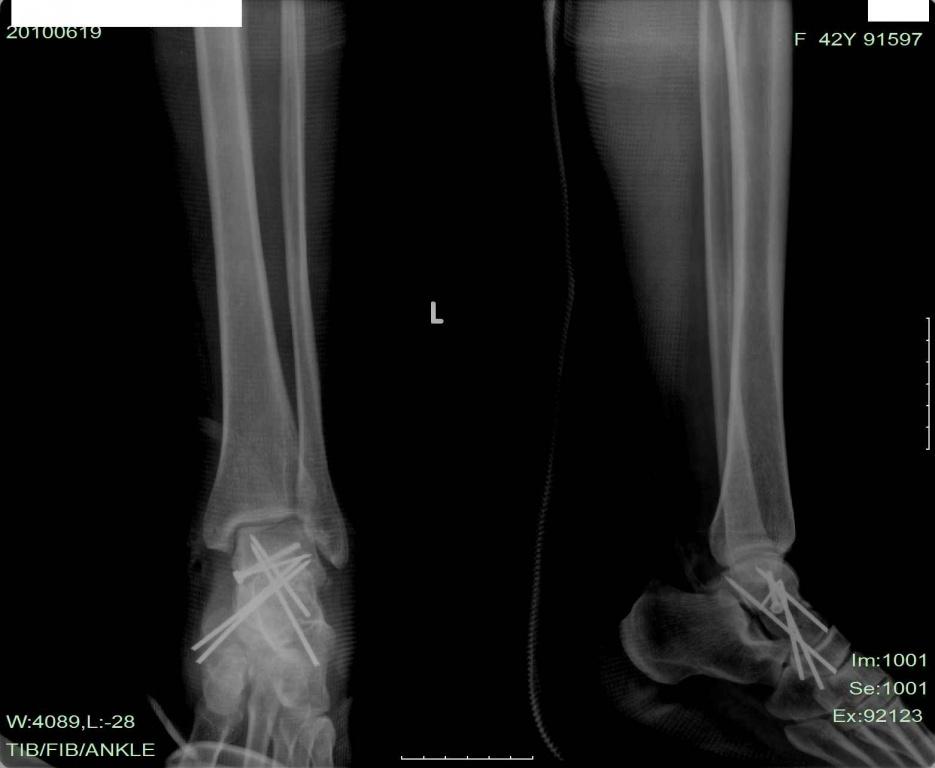

处理:予距骨骨折复位固定,距下关节脱位复位,肌腱复位,胫后神经未修复,伤口闭合,石膏托外固定。